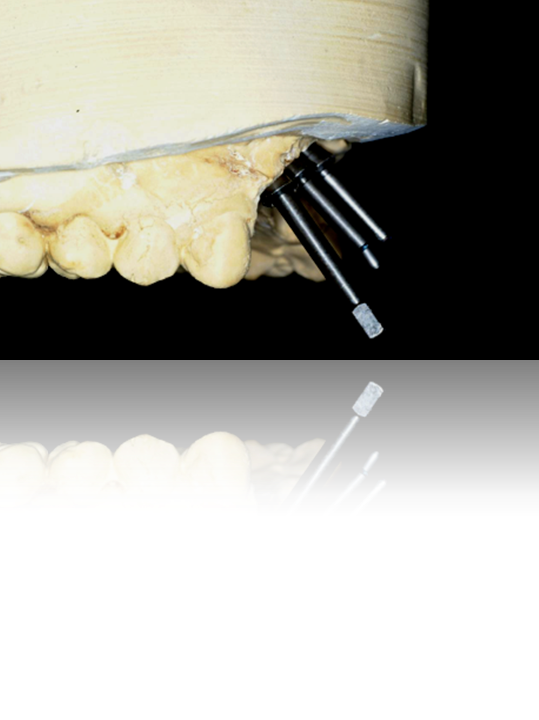

Figure 21. In this case, prefabricated abutments were selected, and the laboratory was instructed to fabricate the crown restorations with an access hole in the middle. Note a paper dowel was placed into the abutment to indicate the placement/location of the access hole.

Figure 21